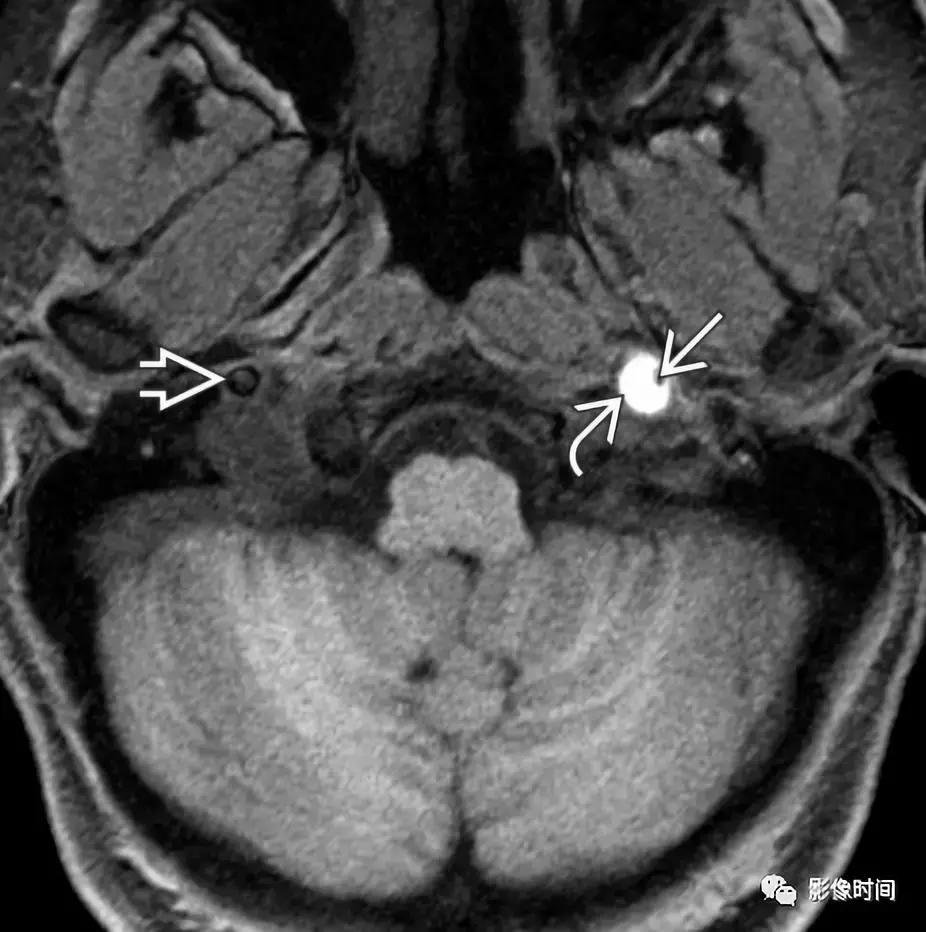

模式图显示颈静脉球瘤富含血管,包绕颅神经伴「虫噬状骨质破坏」。CT 显示颈静脉孔区「蛀虫」的骨质破坏。增强 MRI 显示颈静脉孔区增强肿块 (白色箭头),注意流空信号 (黑色箭头)。